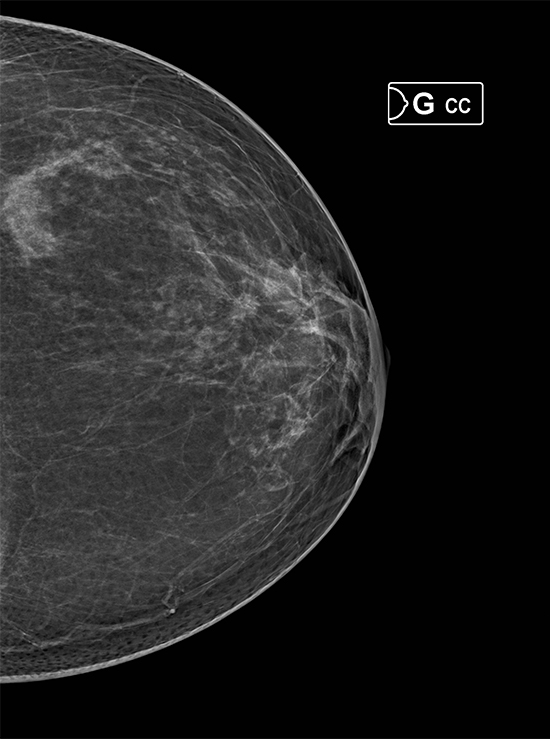

Hera-MI ha desarrollado un potente algoritmo patentado para el soporte de lectura y decisión clínica en mamografía 2D y 3D llamado Breast-Slim View, integrado con tecnología de última generación mediante algoritmos de inteligencia artificial (AI), diseñado como una herramienta para el radiólogo “en su toma de decisiones diaria” esta herramienta es capaz de analizar y comparar una gran cantidad de datos en muy poco tiempo, con la finalidad de identificar áreas de riesgo mediante su innovadora fórmula de doble lectura que todo profesional en imagen diagnóstica necesita.

Incluída dentro de la suite Breast-SlimView®. la "MAMMOGRAPHY TECHNICAL EVALUATION" otorga información al radiólogo para la toma de desiciones mediante el analisis específico del posicionamiento, compresión, densidad mamaria y la dosis de radiación recibida en cada una de las proyecciones.